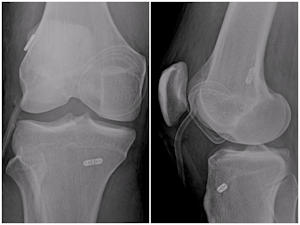

Ön çapraz bağ yaralanmaları çoğunlukla düzgün bir kesi şeklinde değil, bağ saçaklanarak ve parçalanarak kopacak şekilde ortaya çıkar. Bu nedenle bağın dikilerek onarımı mümkün değildir. Ön çapraz bağı onarmak için greft adı verilen, diz çevresi kaslarının kirişleri kullanılır. Elde edilen bu greftler, ön çapraz bağın yapışma yerlerine açılan kemik tünellere uygun gerginlikte yerleştirilir ve iki ucundan tespit edilir. Bu greftler arasında en sık kullanılanlar, dize bükme hareketini yaptıran ve vücutta dört adet olan hamstring kaslarının kirişleridir. Genellikle iki hamstring kasının kirişi elde edilir ve ikiye katlanarak kullanılır. Ön çapraz bağ cerrahisinin başarılı olabilmesi için greft çapının en az 8 mm olması gerektiği gösterilmiştir. İki hamstring kasının kirişleri ikiye katlandığında bu çapa ulaşılır ve geçilir. Ancak hamstring kas kirişlerinin ikisinin kullanılması, özellikle ani sprint ve sıçrama gerektiren sporcularda kas güçsüzlüğüne yol açabilir. Tek hamstring kas kirişinin kullanılması, bu sorunu ortadan kaldırmak için geliştirilmiştir. Dört hamstring kasından sadece birisi greft olarak kullanılır, bu sayede sıçrama ve sprint gücündeki kayıp en aza indirilmiş olur. Kasın kirişi dörde katlanarak 9-11mm çapında ve 7.5 cm uzunluğunda bir greft dokusu elde edilir (Resim 1). Güncel tespit yöntemleri ile bu greftin sağlam tespitini sağlamak mümkündür.